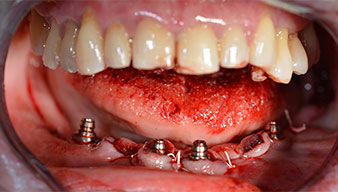

Surgical procedure

After removal of the residual dentition in the mandible, the alveolar crest was exposed from 37 to 47.

The mental foramen was first identified as a limiting anatomical structure and then the cortical bone of the crest was smoothed with the straight handpiece and a large rose-head bur (Fig. 4).